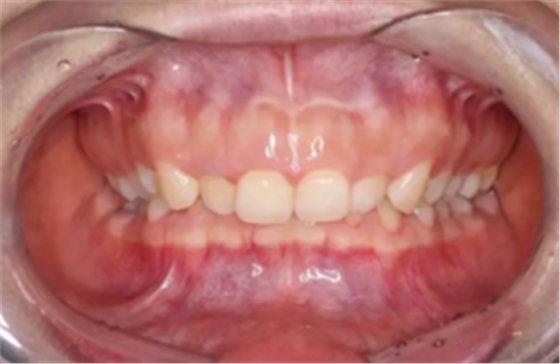

正常情況下,我們的上前牙是蓋在下前牙唇側(cè)3mm內(nèi)的,上下切牙牙軸交角為125°左右,

前牙正常覆合

前牙正常覆蓋